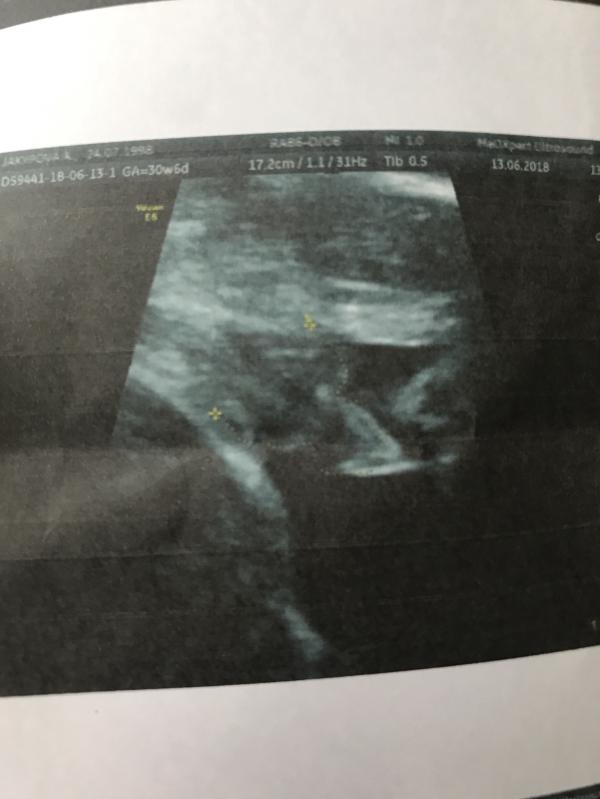

Была на узи и доплере в MedXpert у Келдибекова Алмаза. Лучший узист😍. Задавала все интересующиеся вопросы, говорю: «а на этом узи мне так сказали, а на том вот так». А он в ответ: « а ты отвечай не ваше дело, у меня всё отлично и никого не слушай, пусть не говорят всякий бред, у тебя ведь всё хорошо».😊 Вес плодов 1700 и 1600

Оба в головном предлежании😍😍😍(уговорила всё таки перевернуться☺️). На фото колокольчик сыночка😍☺️